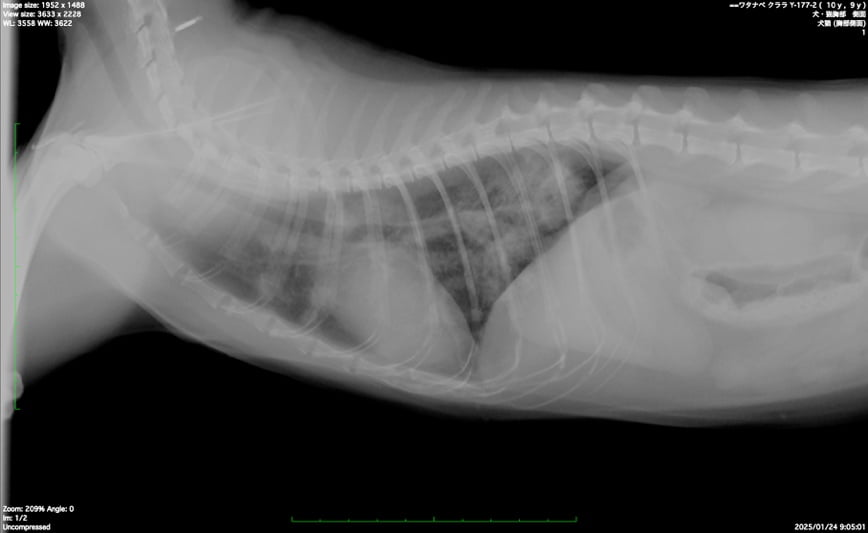

同一症例のレントゲン検査と気管支鏡検査